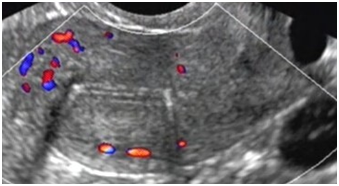

Pelvic ultrasound showed a normal size uterus, measuring 48mm in size, endometrial thickness of 4mm, cervical length of 27mm, presence of intrauterine device (IUD) and normal bilateral adnexa, as well as nabothian cyst of the cervix (Figure 1).

Figure 1 Pelvic Ultrasound: showing a normal size uterus measuring 48 mm in size, endometrial thickness of 4mm, and presence of intrauterine device (IUD).